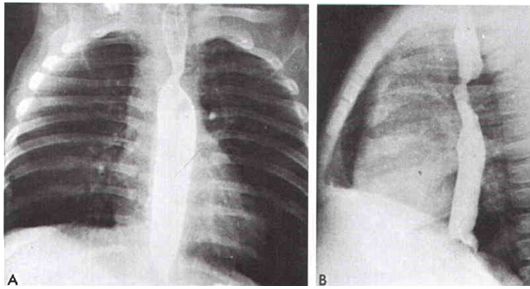

41. 一名5個月男嬰被發現呼吸困難合併喘鳴聲 (stridor) 及吞嚥困難。食道攝影如圖示。下列何者為最可能的心臟問題? (A)右主動脈弓併左開放性動脈導管 (right arch & left PDA)。 (B)肺動脈吊帶 (PA sling)。 (C)持續第5主動脈弓(persistent fifth arch)。 (D)雙主動脈弓(double aortic arch)。 (E)右主動脈弓併左鎖骨動脈異常源出。